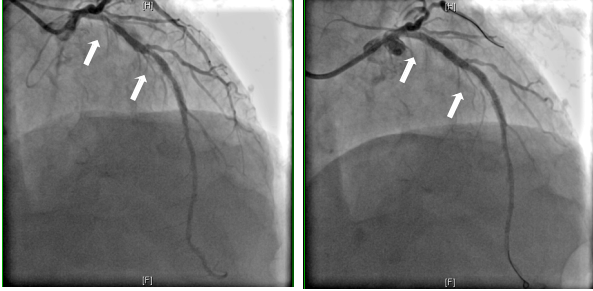

目前,冠状动脉介入治疗已成为冠心病的常见治疗方案,但随之而来的支架内再狭窄成为了困扰术后患者的重要难题。患者孟先生4年前在外院因急性广泛前壁心肌梗死于,前降支植入支架,2年前出现阵发性胸痛,使用普通球囊扩张后症状有改善。近期,他又出现反复胸闷、胸痛的症状,冠状动脉造影复查提示,冠脉血管支架再次出现严重狭窄。另一位患者姚先生,1年前因急性下壁心肌梗死于右冠状动脉植入支架,近期再次复查,同样提示了右冠中段支架内再狭窄。

11月19日,心内科介入团队为两位患者先后实施手术,顺利将导丝通过支架内再狭窄病变,在用普通球囊及切割球囊对患者病变进行预扩张后,将药物球囊送至病变区域再扩张,进行充分活性药物释放治疗,冠状动脉造影显示支架内再狭窄改善,心脏恢复了正常血流灌注,手术顺利,治疗效果明显。